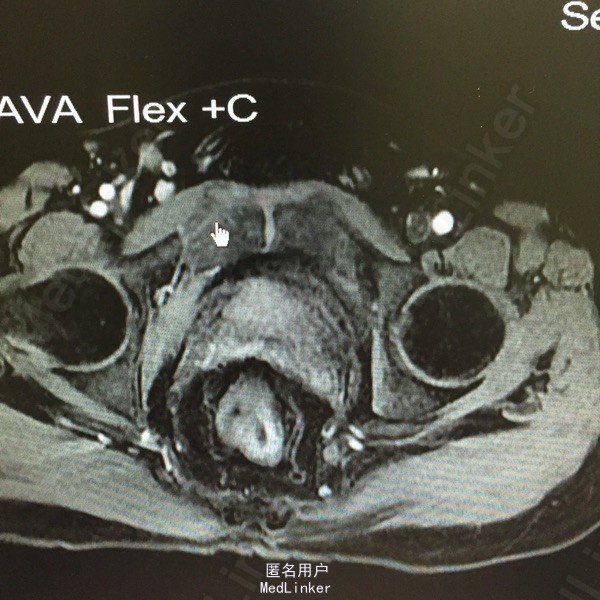

查体:kc位,2,4点及外口,触痛阳性,入指未及条索样物。 MR:右骨盆直肠窝,坐骨直肠窝脓肿

考虑高位复杂肛瘘